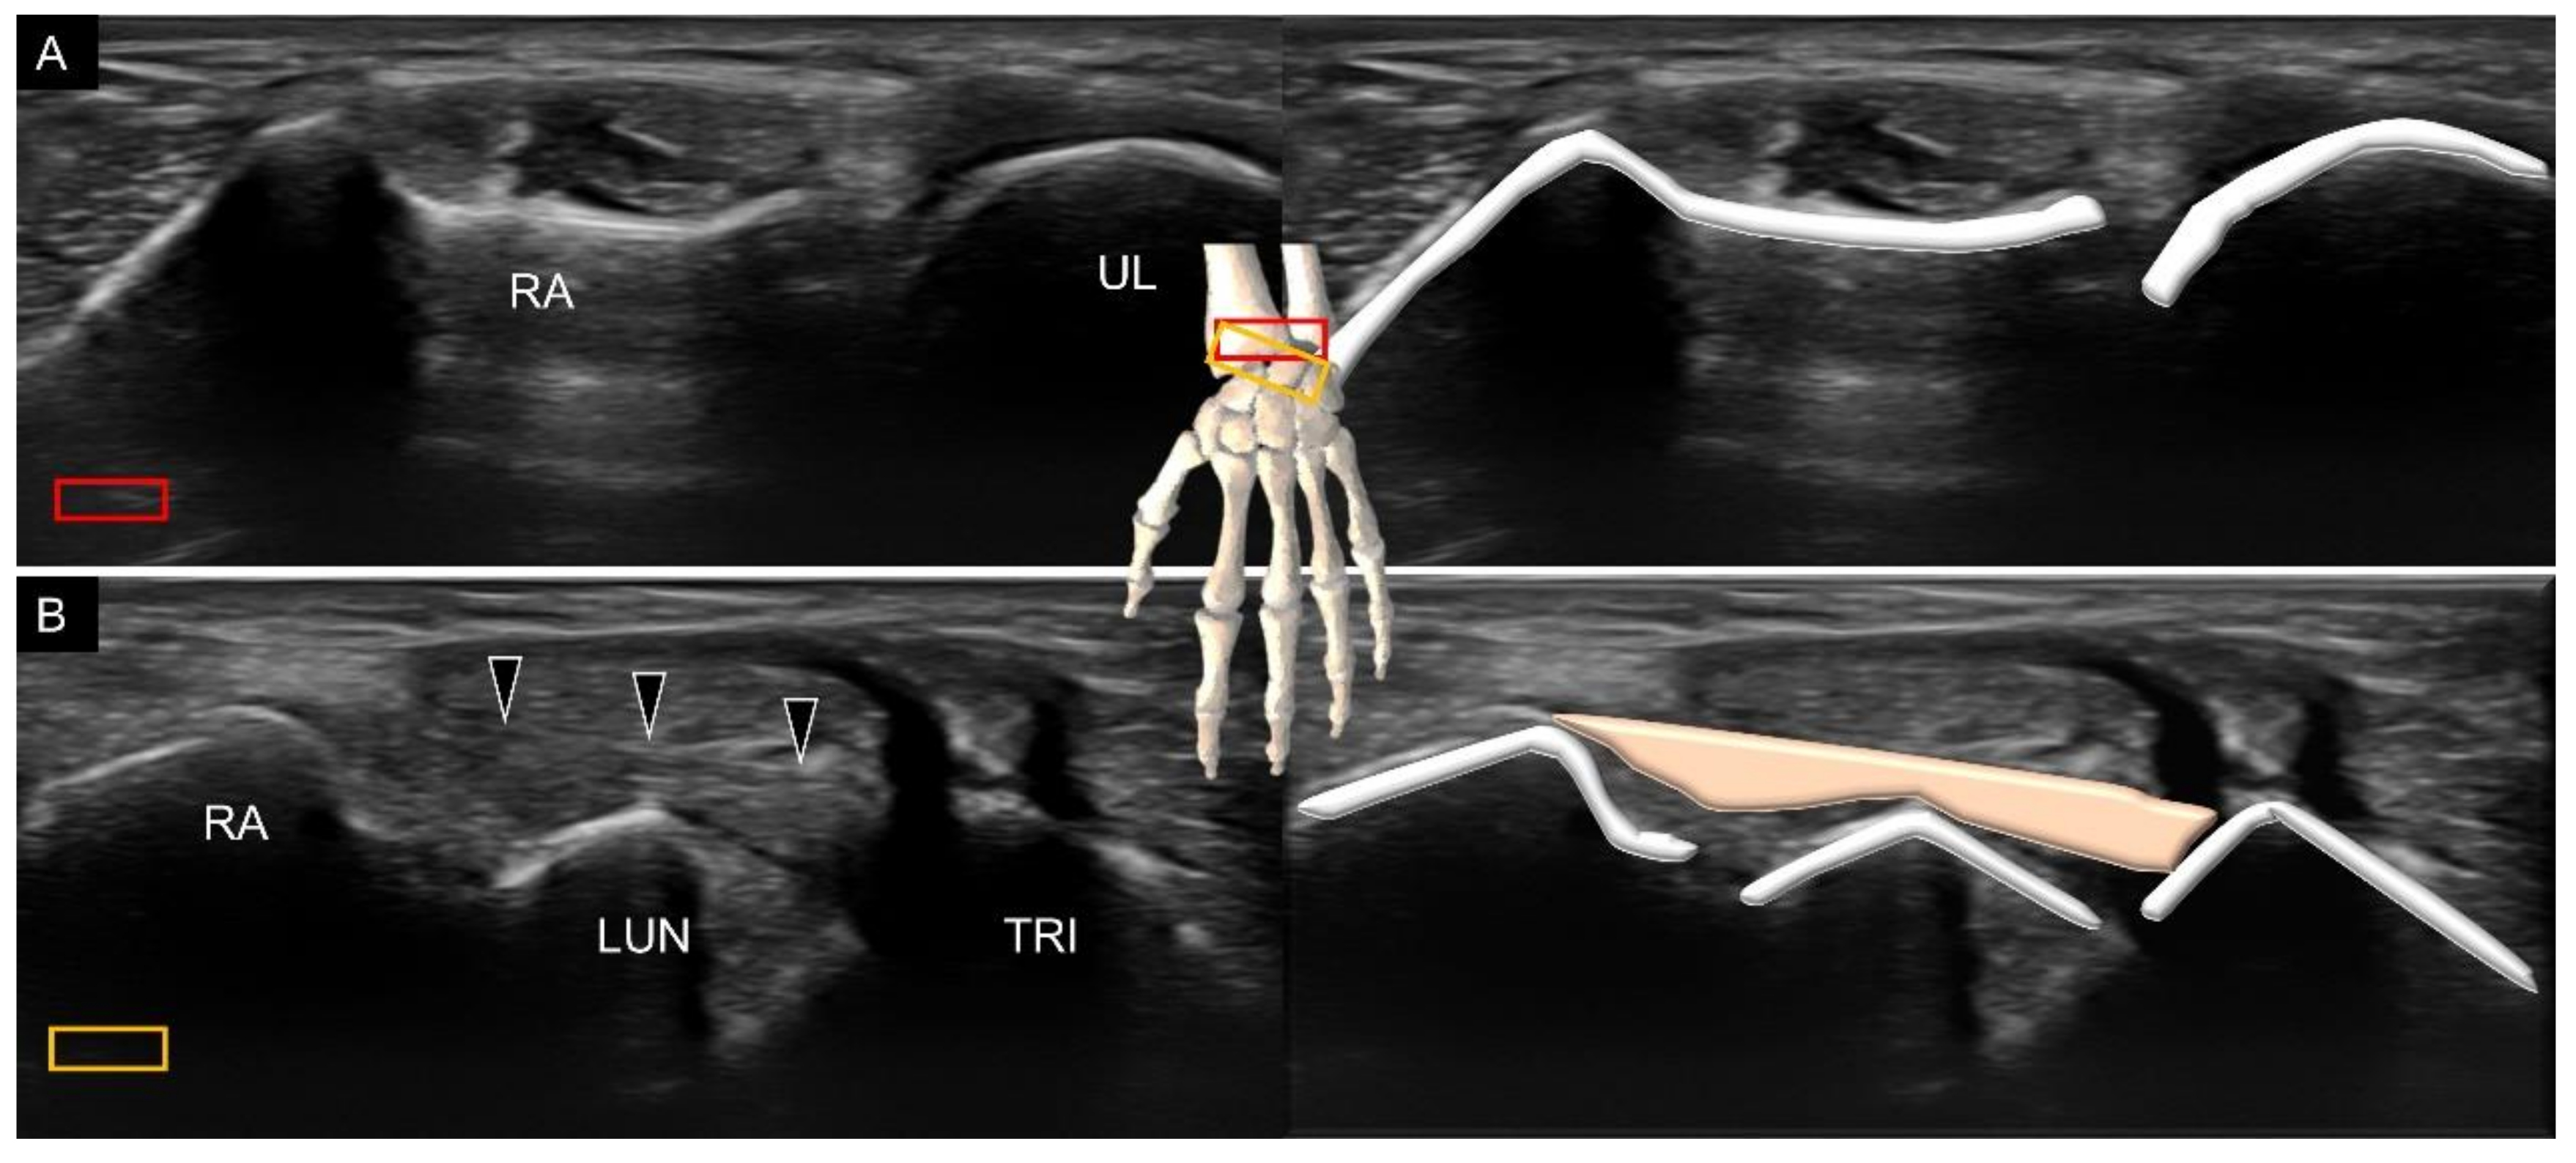

3.1. Attachment to the Capitate

5. Sonoanatomy of Dorsal Extrinsic Carpal Ligaments

Attachment to the Triquetrum

6. Sonoanatomy of Dorsal Intrinsic Carpal Ligaments